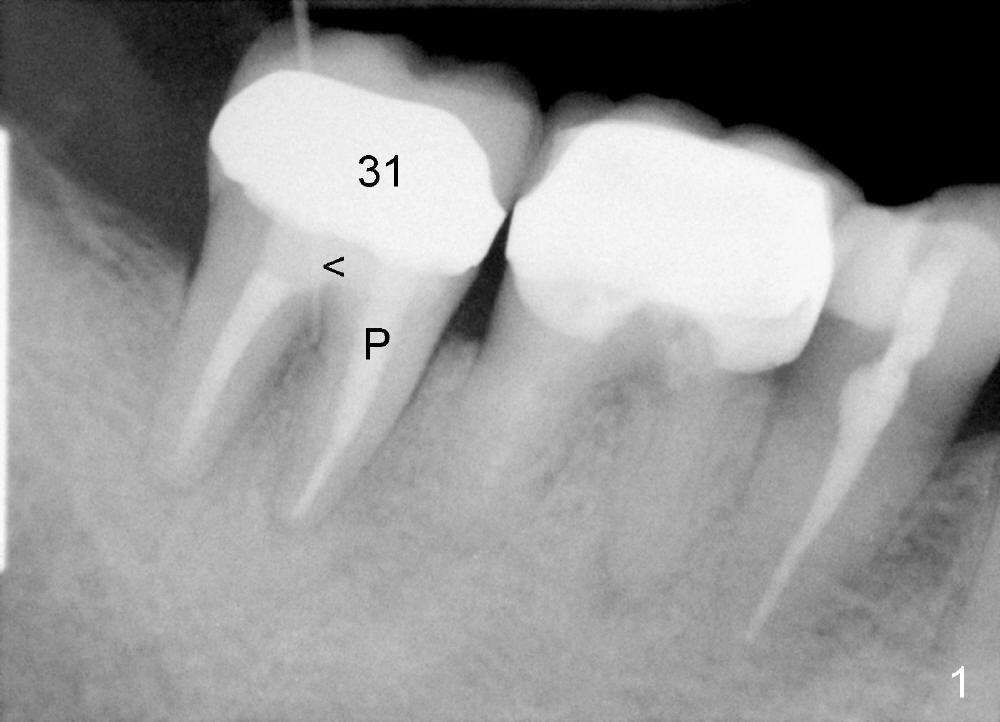

A 51-year-old man has experienced pain and swelling in the lower right 2nd molar for 7 months (Fig.1, P: post in the mesial root; <: gutta percha inserted into a buccal fistula). Fig.2 is taken immediately before extraction (<: purulent discharge from the mesiobuccal fistula) and immediate implant (Fig.3 implant design: 7x14 mm). A vertical root fracture is noted in the mesial root (Fig.4: lingual view). The septum is in fact absent, as compared to Fig.1. The mesiobuccal plate is low; the osteotomy starts lingual to the center of the socket. Fig.5 shows a 4.5x17 mm tap in place: approximately 3.5 mm in the new bone (~2.5 mm from the inferior alveolar canal). When a 7x17 mm tap (14 mm from the gingival margin) is placed in the socket, it looks relatively small. Fig.6 shows a 8x14 mm implant in place with a small gap distally. Mineralized cancellous allograft and Osteogen mixture is placed mainly buccally, followed by a thin strip of collagen dressing and sutures (Fig.7); an abutment (A) is placed to keep perio dressing in place. The perio dressing does not stay long. The buccal portion dislodges by itself 5 days postop. The lingual portion is removed in clinic. New dressing is going to be re-applied, because the buccal wound has not completely healed (Fig.8 <, albeit asymptomatic) with partial exposure of the bone graft (*). Why is the dressing lost so early? The abutment is not long enough; there is plenty of occlusal clearance (Fig.9 arrows). A longer abutment is used to increase mechanical retention for perio dressing (Fig.10). By the time the second perio dressing dislodges, the wound has healed (Fig.11, 13 days postop).

Fig.12 show root fracture associated with mesiobuccal post of the 2nd molar. In contrast the lower right 2nd premolar is intact without crown after root canal therapy. It appears that the post weakens the root.